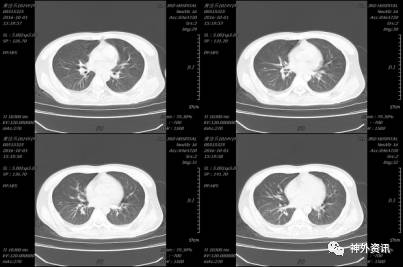

2015-12-02 12:33 伤后1小时我院急诊科复查头颅CT(2015-12-02 12:33):

入科后急诊在全麻下行去骨瓣减压及硬膜下血肿清除术,植入脑实质内颅内压监测,术后患者颅内压正常范围,生命体征平稳,术后第二日复查头颅CT及胸部CT(术后约14小时,2015-12-03 09:33):